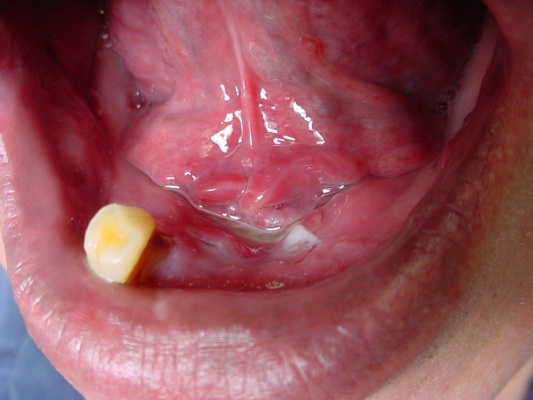

Cancers Of The Floor Of The Mouth

Floor Of The Mouth Cancer

Floor Of The Mouth Cancer Causes Symptoms Treatment Survival

Malignant Tumors Of The Floor Of The Mouth Background

Cancers Of The Floor Of The Mouth

Lesion On The Anterior Floor Of The Mouth With Irregular

Cancers Of The Floor Of The Mouth